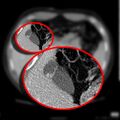

CT scan showing a phrygian cap

In medicine, a Phrygian cap is the folded portion of some gallbladders that resembles the Phrygian cap (a soft conical cap with the top pulled forward, associated in antiquity with the inhabitants of Phrygia, a region of central Anatolia). It is a normal anatomical variant seen in 1-6% of patients.[1] It is caused by a fold in the gallbladder where the gallbladder fundus joins the gallbladder body.[2] Apart from the chance of being mistaken for stones on a sonogram, it has no other medical implications nor does it predispose one to other diseases.[citation needed] However, due to potential decrease in bile flow, it may warrant a preventive removal of the gallbladder. [citation needed]